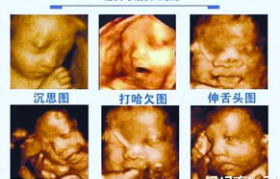

彩超检查作为现代医疗诊断的重要手段,其费用因多种因素而异。本文将全面解析彩超的价格构成、影响因素、不...

本文将全面解析B超检查的价格因素,包括不同部位B超费用差异、医院等级影响、医保报销政策以及如何选择性...